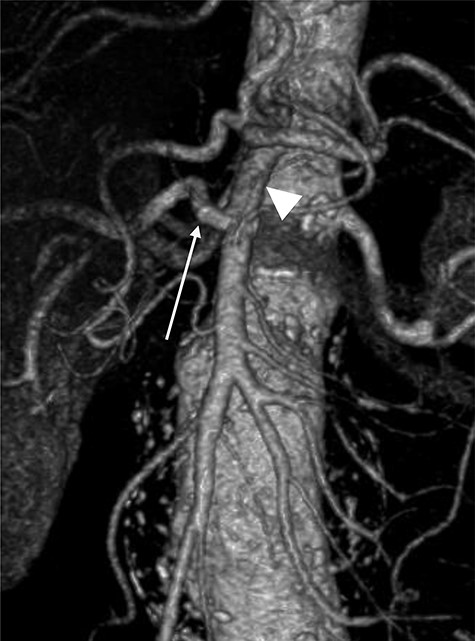

A 78-year-old gentleman admitted for elective FEVAR to treat his CT confirmed 5.7 cm juxtarenal AAA. He was not suitable for open repair and initially offered the option of no intervention due to ongoing comorbidities resulting in poor cardiopulmonary function; however, he was keen to proceed with surgery. From pre-implant planning CT angiogram (CTA), infrarenal endograft was unsuitable for EVAR due to reverse conicity and unhealthy infrarenal aortic neck (Fig. 1); therefore, FEVAR was chosen. RRHA from SMA was also seen in pre-operative CTA but not reported (Fig. 2).

Pre-implant planning CTA showing unhealthy infrarenal aortic neck.

Pre-operative CTA showing healthy SMA (arrowhead) with RRHA (arrow).